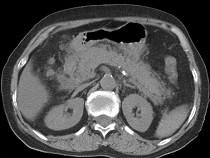

问题 男,30岁,上腹部剧痛,恶心呕吐,压痛反跳痛,血细胞计数升高,血和尿淀粉酶升高,影像表现如图,最可能的诊断是什么 ( )

选项 A.急性肠梗阻 B.胃溃疡穿孔 C.胰腺癌 D.急性胰腺炎 E.慢性胰腺炎

答案 D